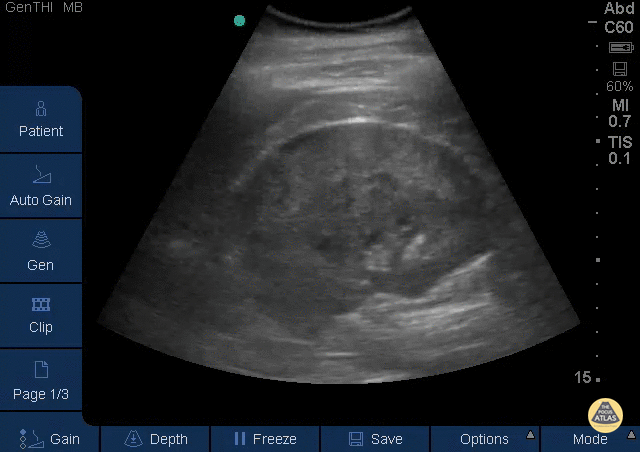

Renal/GU - Perinephric Hematoma

This is a longitudinal view of the right kidney in a patient who presented with sudden, severe right flank pain. There was no history of trauma. No gross hematuria. The patient’s pain was difficult to control with analgesics and bedside ultrasound revealed apparent spontaneous perinephric hematoma. Therese Mead, DO Emergency Physician